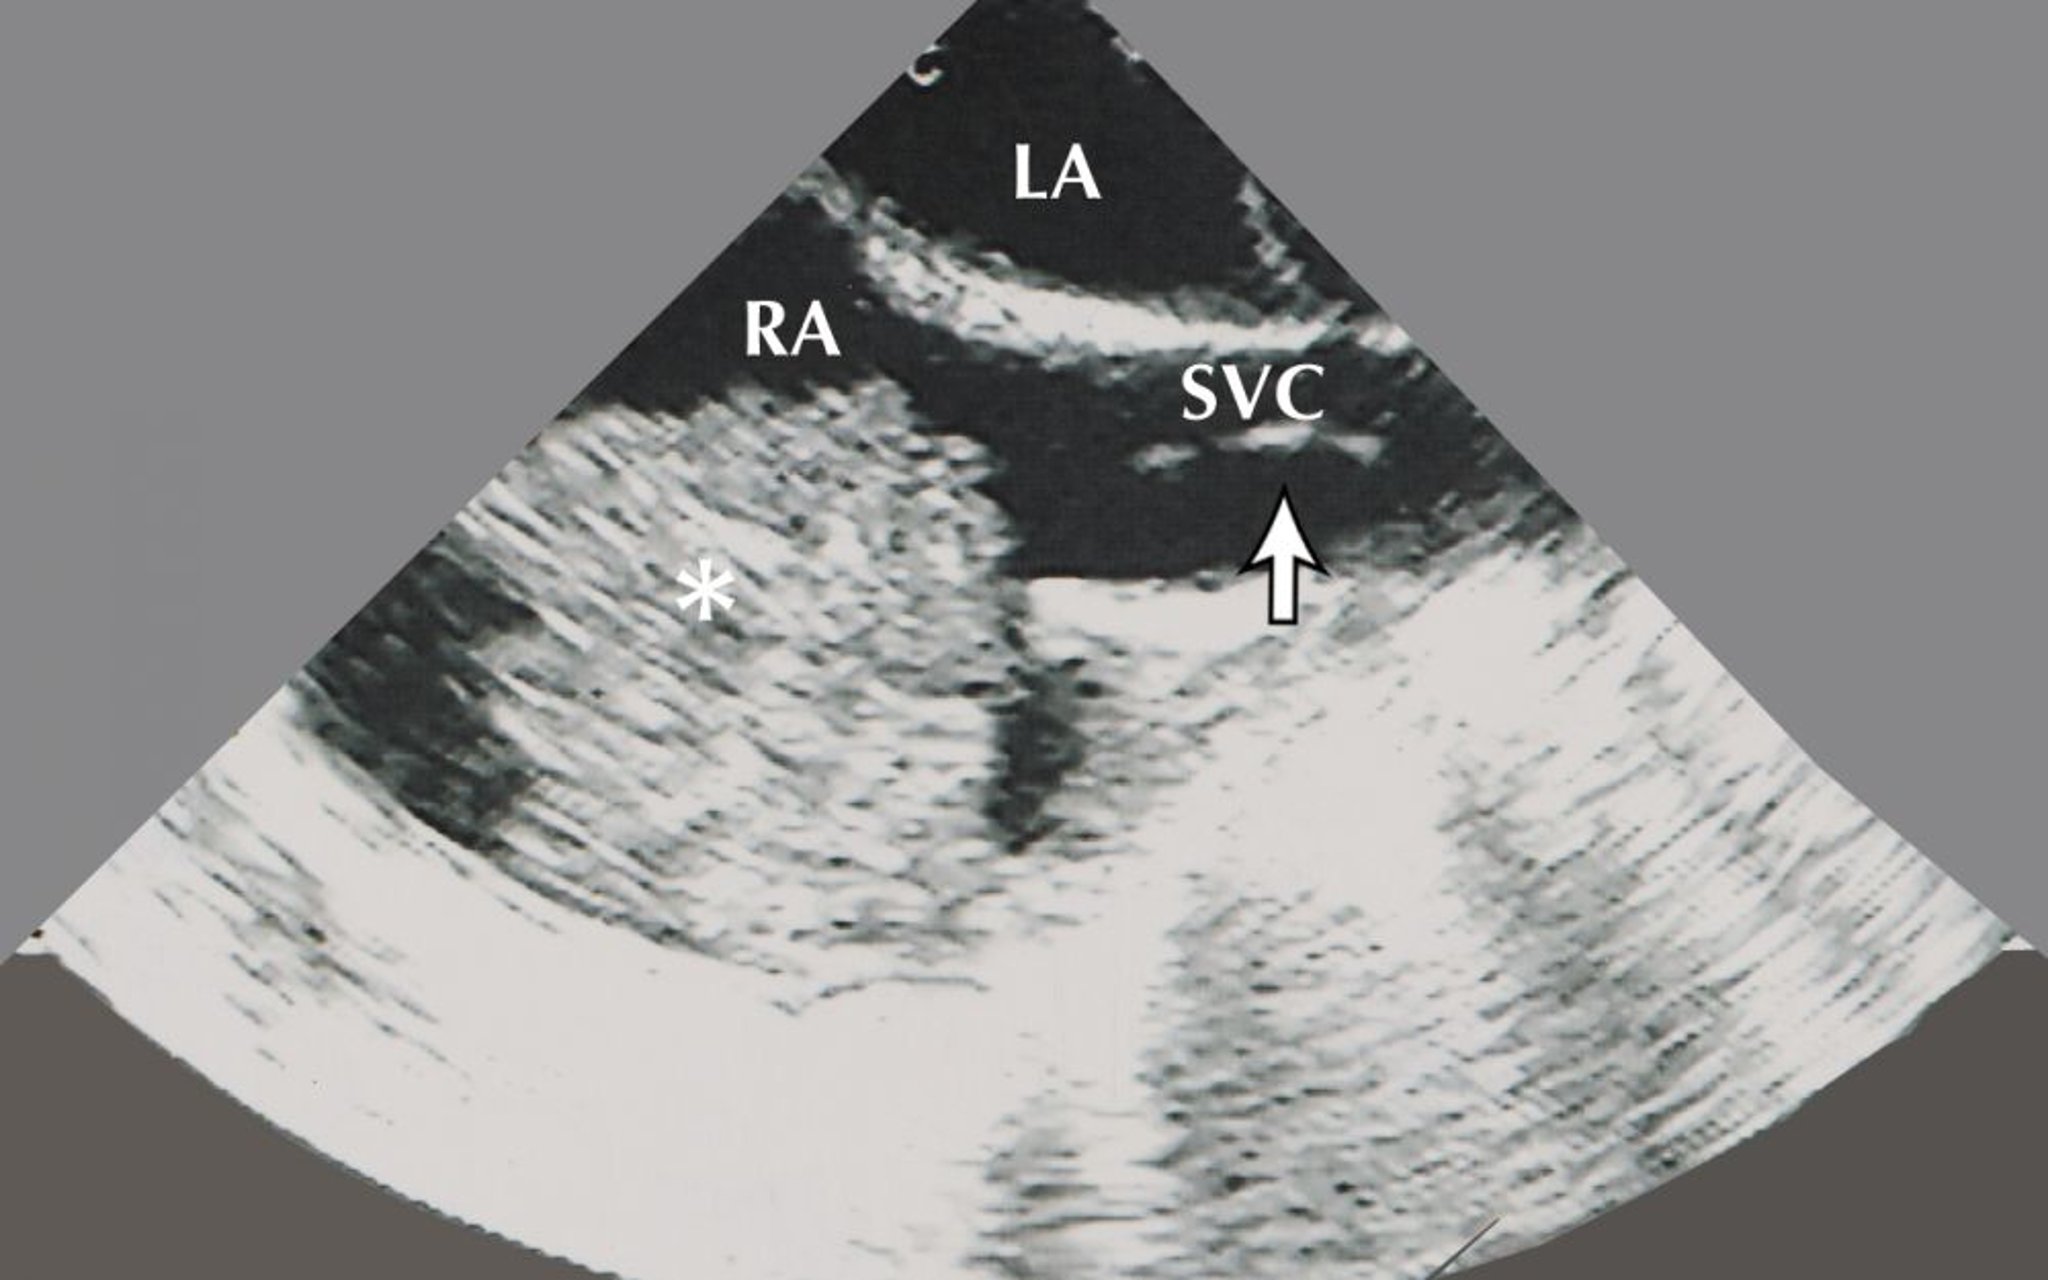

Mixoma atrial (ecocardiograma)

Essa imagem mostra um mixoma atrial (indicado pelo asterisco) no átrio direito (AD). Também estão visíveis nessa imagem ecocardiográfica o átrio esquerdo (AE) e um biótomo de biópsia (indicado pela seta) na veia cava superior (VCS).